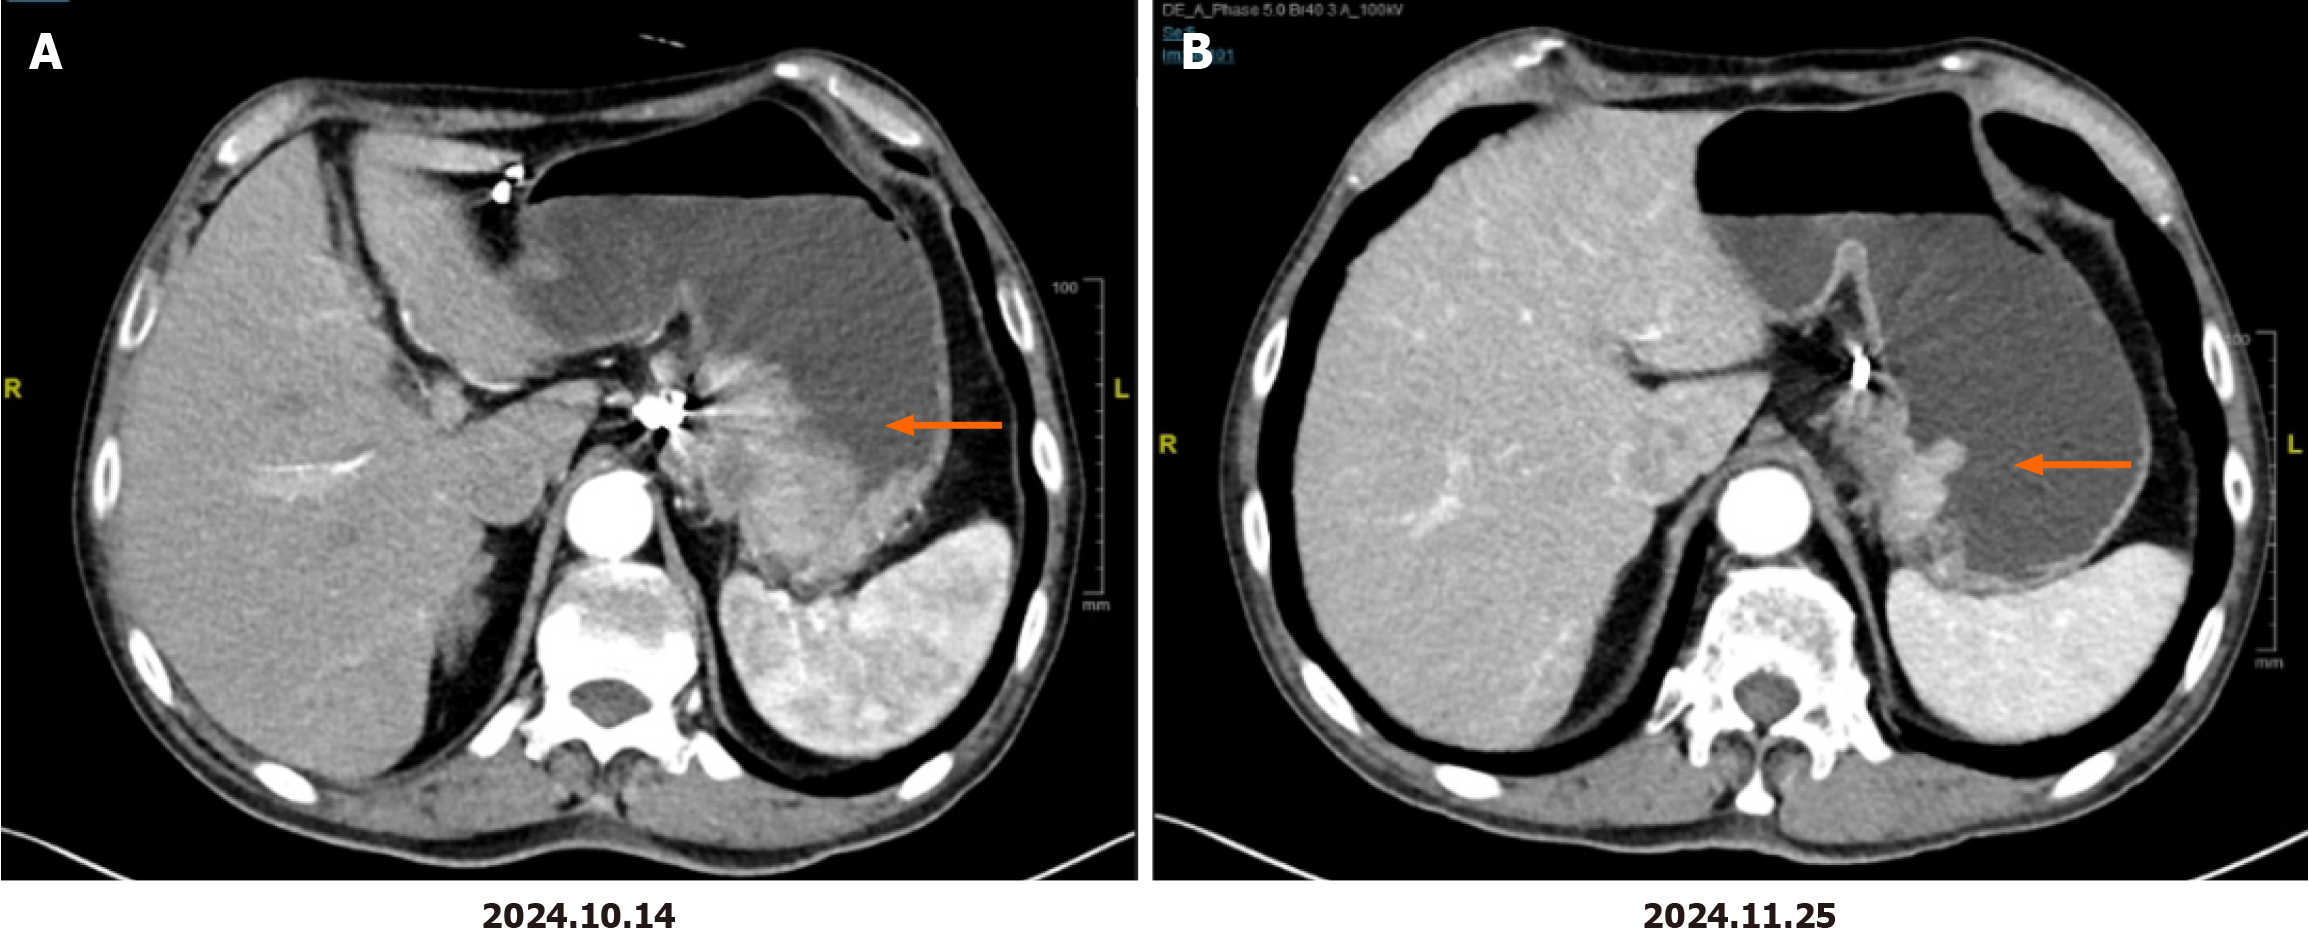

The patient received four cycles of oxaliplatin, S-1 (SOX) combined with trastuzumab treatment in our department starting on October 31, 2024. The specific SOX regimen was as follows: Oxaliplatin at a dose of 130 mg/m2 (2-hour intravenous infusion) on day 1 and S-1 taken orally at a dose of 120 mg/day for body surface areas of > 1.5 m2 on days 1-14 every three weeks. The initial trastuzumab dose was 8 mg/kg, and the subsequent dose was 6 mg/kg on day 1 and then every three weeks. The patient's medication dosage has not yet been reduced. The adverse events were grade 1 neurotoxicity and grade 1 nausea. No drug-related myelosuppression or cardiotoxicity occurred. Follow-up imaging after two cycles of treatment revealed a significant improvement in gastric wall thickening at the lesser curvature and a reduction of adjacent lymph node size, achieving a partial response (PR) that was maintained after four cycles (Figure 1). The patient reported marked improvement in fatigue symptoms. On February 6, 2025, the patient underwent robot-assisted radical distal gastrectomy at our hospital. Postoperative pathology results confirmed moderately differentiated adenocarcinoma (Lauren classification: Intestinal type) infiltrating the muscular layer and subserosa, with extensive foam cell aggregation, fibrous tissue hyperplasia, and inflammatory cell infiltration. The tumor occupied 20% of the tumor bed area, which was consistent with partial treatment response (College of American Pathologists grade 2), without serosal invasion, with negative surgical margins, no evidence of neural or vascular invasion, and lymph node metastasis (1/46). Final pathological staging was pT3N1, stage II.